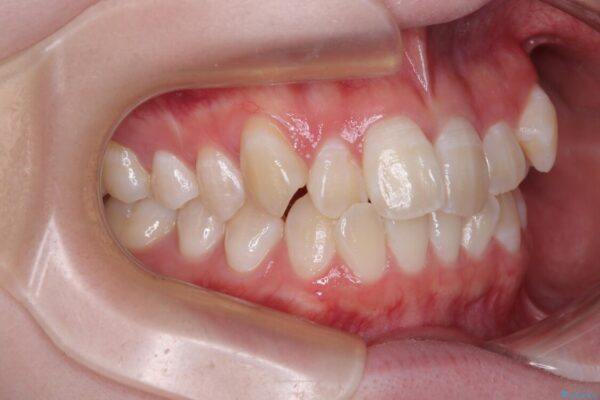

治療途中

• 【モニター】前歯のデコボコをスッキリ解消!目立ちにくいワイヤー矯正でスピーディに治療完了 治療途中画像

マウスピース矯正も検討されていましたが、「装着時間の自己管理が難しそう」「なるべく早く治療を終えたい」とのご希望から、ワイヤー矯正を選択されました。

目立ちにくさと費用のバランスを考慮し、プラスチックブラケット+メタルワイヤーを採用。日常生活でも装置の存在感を気にせずお過ごしいただけます。